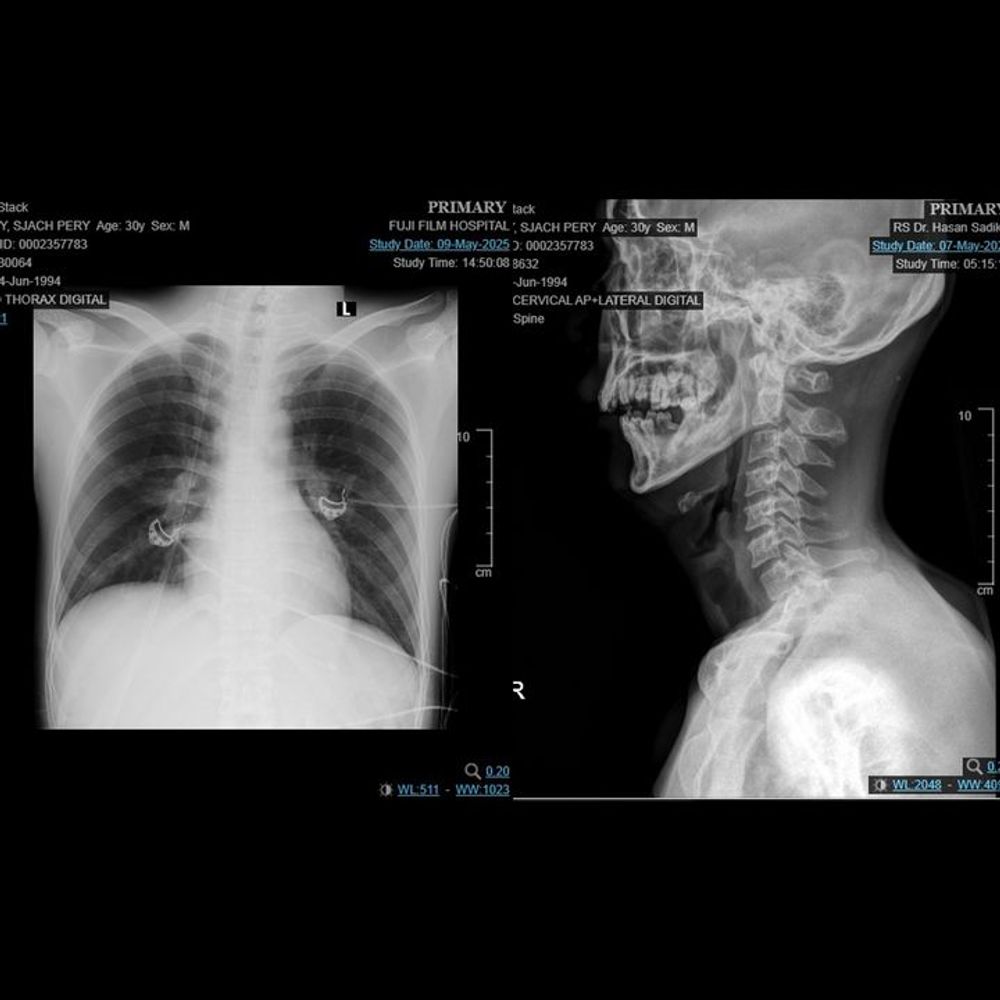

Late at night, a father received the phone call that shattered his world — his beloved son, Robby, had been in a horrific traffic accident. He was found unconscious, his head bleeding heavily, his life hanging by a thread. Doctors rushed him into the emergency room, explaining that only immediate surgery and intensive treatment could give him a chance to survive.